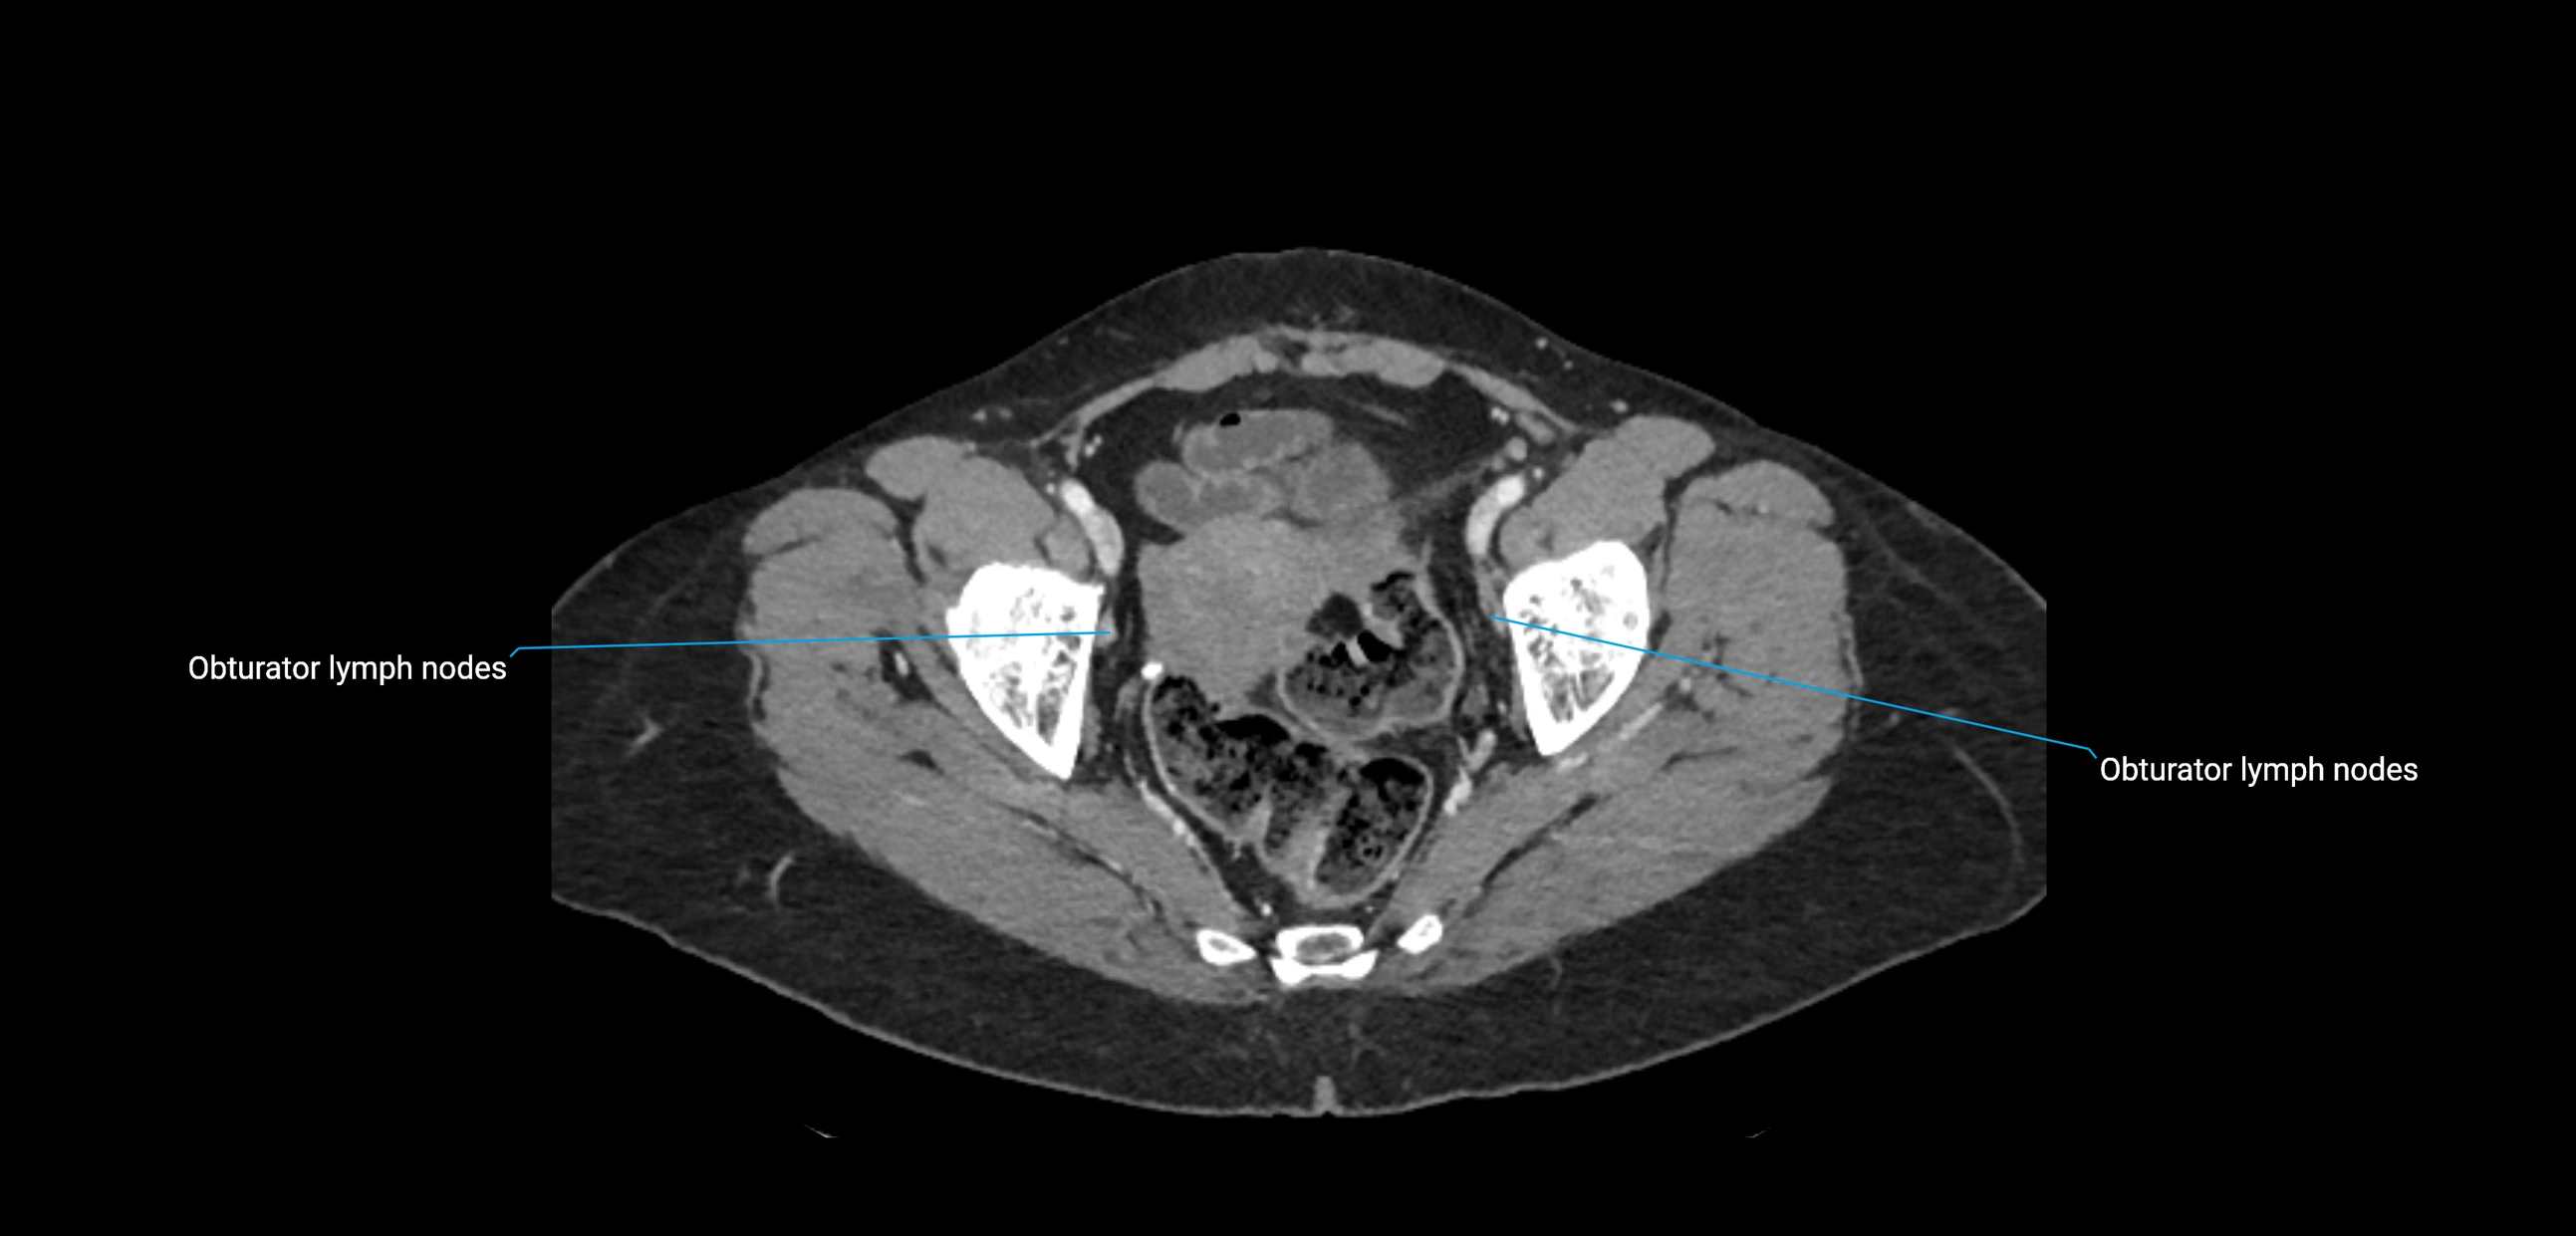

CT Appearance

CT Post-Contrast:

• Normal nodes enhance homogeneously

• Malignant nodes may show heterogeneous enhancement, central necrosis, or conglomerate formation

• Size >1 cm short axis is suspicious, though morphology and distribution are equally important

CT Venography (CTV):

• Demonstrates nodal encasement or compression of adjacent vessels (aorta, IVC, renal veins)

• Useful in staging testicular and ovarian malignancies

• Provides 3D reconstructions for retroperitoneal lymph node dissection planning